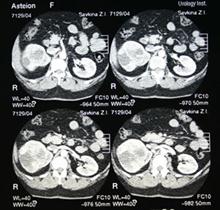

Рис. 11. Компьютерный томограф и снимки томографии брюшной полости